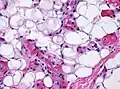

The cause is unknown.[1] It has all other features of a typical lipoma.[2]: 624 [3] When surgically removed, it appears yellow-red with a capsule.[1] Under the microscope, it features mature adipocytes and branching vessels of capillary size, which typically contain fibrin thrombi.[1]

Small vessels in adipose tissue -

The vessels typically contain hyaline or fibrin (pictured) thrombi[4] -